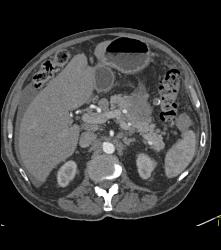

Multiple Incidental Pulmonary Emboli (PEs) in Patient With Pancreatic Cancer